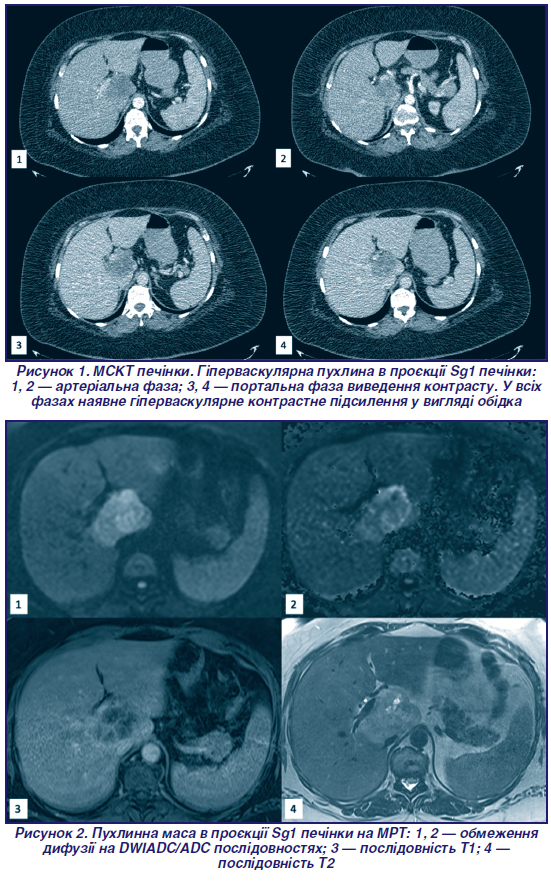

На МСКТ органiв грудної (рис. 1), черевної порожнини та малого таза з внутрiшньовенним контрастуванням (Йогексол 350) вiзуалiзується помiрно збiльшена печiнка (кранiокаудальний розмiр 186 мм), контури рiвнi, чiткi, щiльнiсть паренхiми не знижена. У проєкцiї Sg1 визначається об’ємне гiповаскулярне утворення 48 × 47 × 44 мм, з бугристим контуром, неоднорiдної структури, неоднорiдним гiперваскулярним контрастним пiдсиленням у виглядi обiдка у всi фази контрастування. Дотичне до портальної вени з легким пiдтисненням її та втратою розмежувальних прошаркiв. У воротах печiнки, парааортально, парагастрально та парапанкреатично визначаються множиннi лiмфатичнi вузли до 6 мм. Висновок: утворення може вiдповiдати абсцесу, диференцiювати з фiброламелярною гепатоцелюлярною карциномою. На рiвнi органiв грудної порожнини ознак метастатичного ураження не виявлено. Рекомендовано дообстеження — МРТ печiнки.

На МРТ печiнки (рис. 2) з внутрiшньовенним контрастуванням (гадолiнiй) вiзуалiзується вогнище з високими показниками рестрикцiї дифузiї DWI/ADC, периферичним накопиченням контрасту. Диференцiйний дiагноз згiдно з висновками КТ та МРТ: абсцес та фiброламелярна карцинома, абсцес та пухлинний процес вiдповiдно.

Складнощi дiагностики сВХК пов’язанi з тим, що пухлина може бути асимптоматичною або проявляти себе неспецифiчними симптомами, як-от: втрата маси тіла, втома, тошнота, лихоманка, бiль у животi [3]. У нашому випадку у пацiєнтки була клiнiчна картина, що нагадувала абсцес і супроводжувалась щоденним пiдйомом температури до фiбрильних цифр. У випадку сВХК серологiчнi маркери, характернi для ВХК, втрачають значення. Так, у вивчених нами джерелах описано вiдсутнiсть елевацiї АФП, СА 19-9, РЕА та PIVKA-II у бiльшостi пацiєнтiв із сВХК [2, 6, 10, 11], що збігається з результатами обстеження нашої пацiєнтки. Бiльше того, данi радiологiчних методiв візуалізації також не є специфiчними при сВХК. Дослiдники вказують на наявнiсть у сВХК патернів, характерних для гепатоцелюлярної карциноми, — периферiйного пiдсилення та раннього вимивання контрасту в венозну фазу [8, 12–14]. В описаному нами випадку, окрiм цих ознак, на МСКТ та МРТ спостерiгали змiни, характернi для абсцесу печiнки, що найбiльш імовірно було пов’язано iз центральним некрозом пухлини.